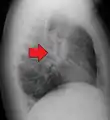

Hilar adenopathy especially on the person's left (AP CXR)

Hilar adenopathy especially on the person's left (lateral CXR)

Hilar adenopathy especially on the person's left (coronal CT)

Hilar adenopathy especially on the person's left (transverse CT)